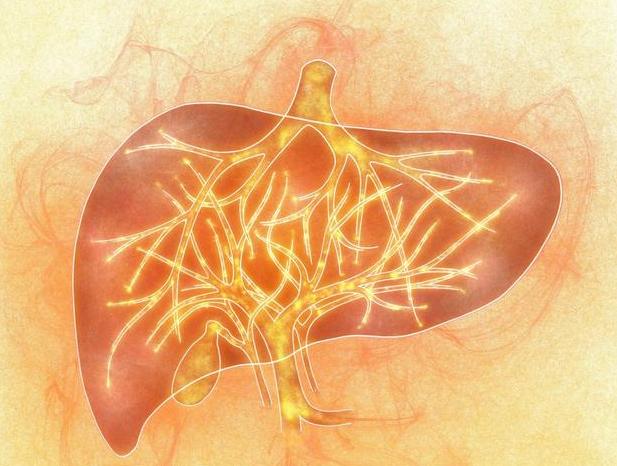

肝臟是我們體內的代謝器官,除了有解毒的作用以外,

還可以幫助我們去氧化、儲存肝醣和合成分泌性蛋白質。

另外,肝臟和膽囊的關係也比較密切,肝臟也是最大的消化腺,可以分泌出膽汁。

所以肝臟對我們的身體健康非常重要,肝臟健康,我們就會生活無憂。